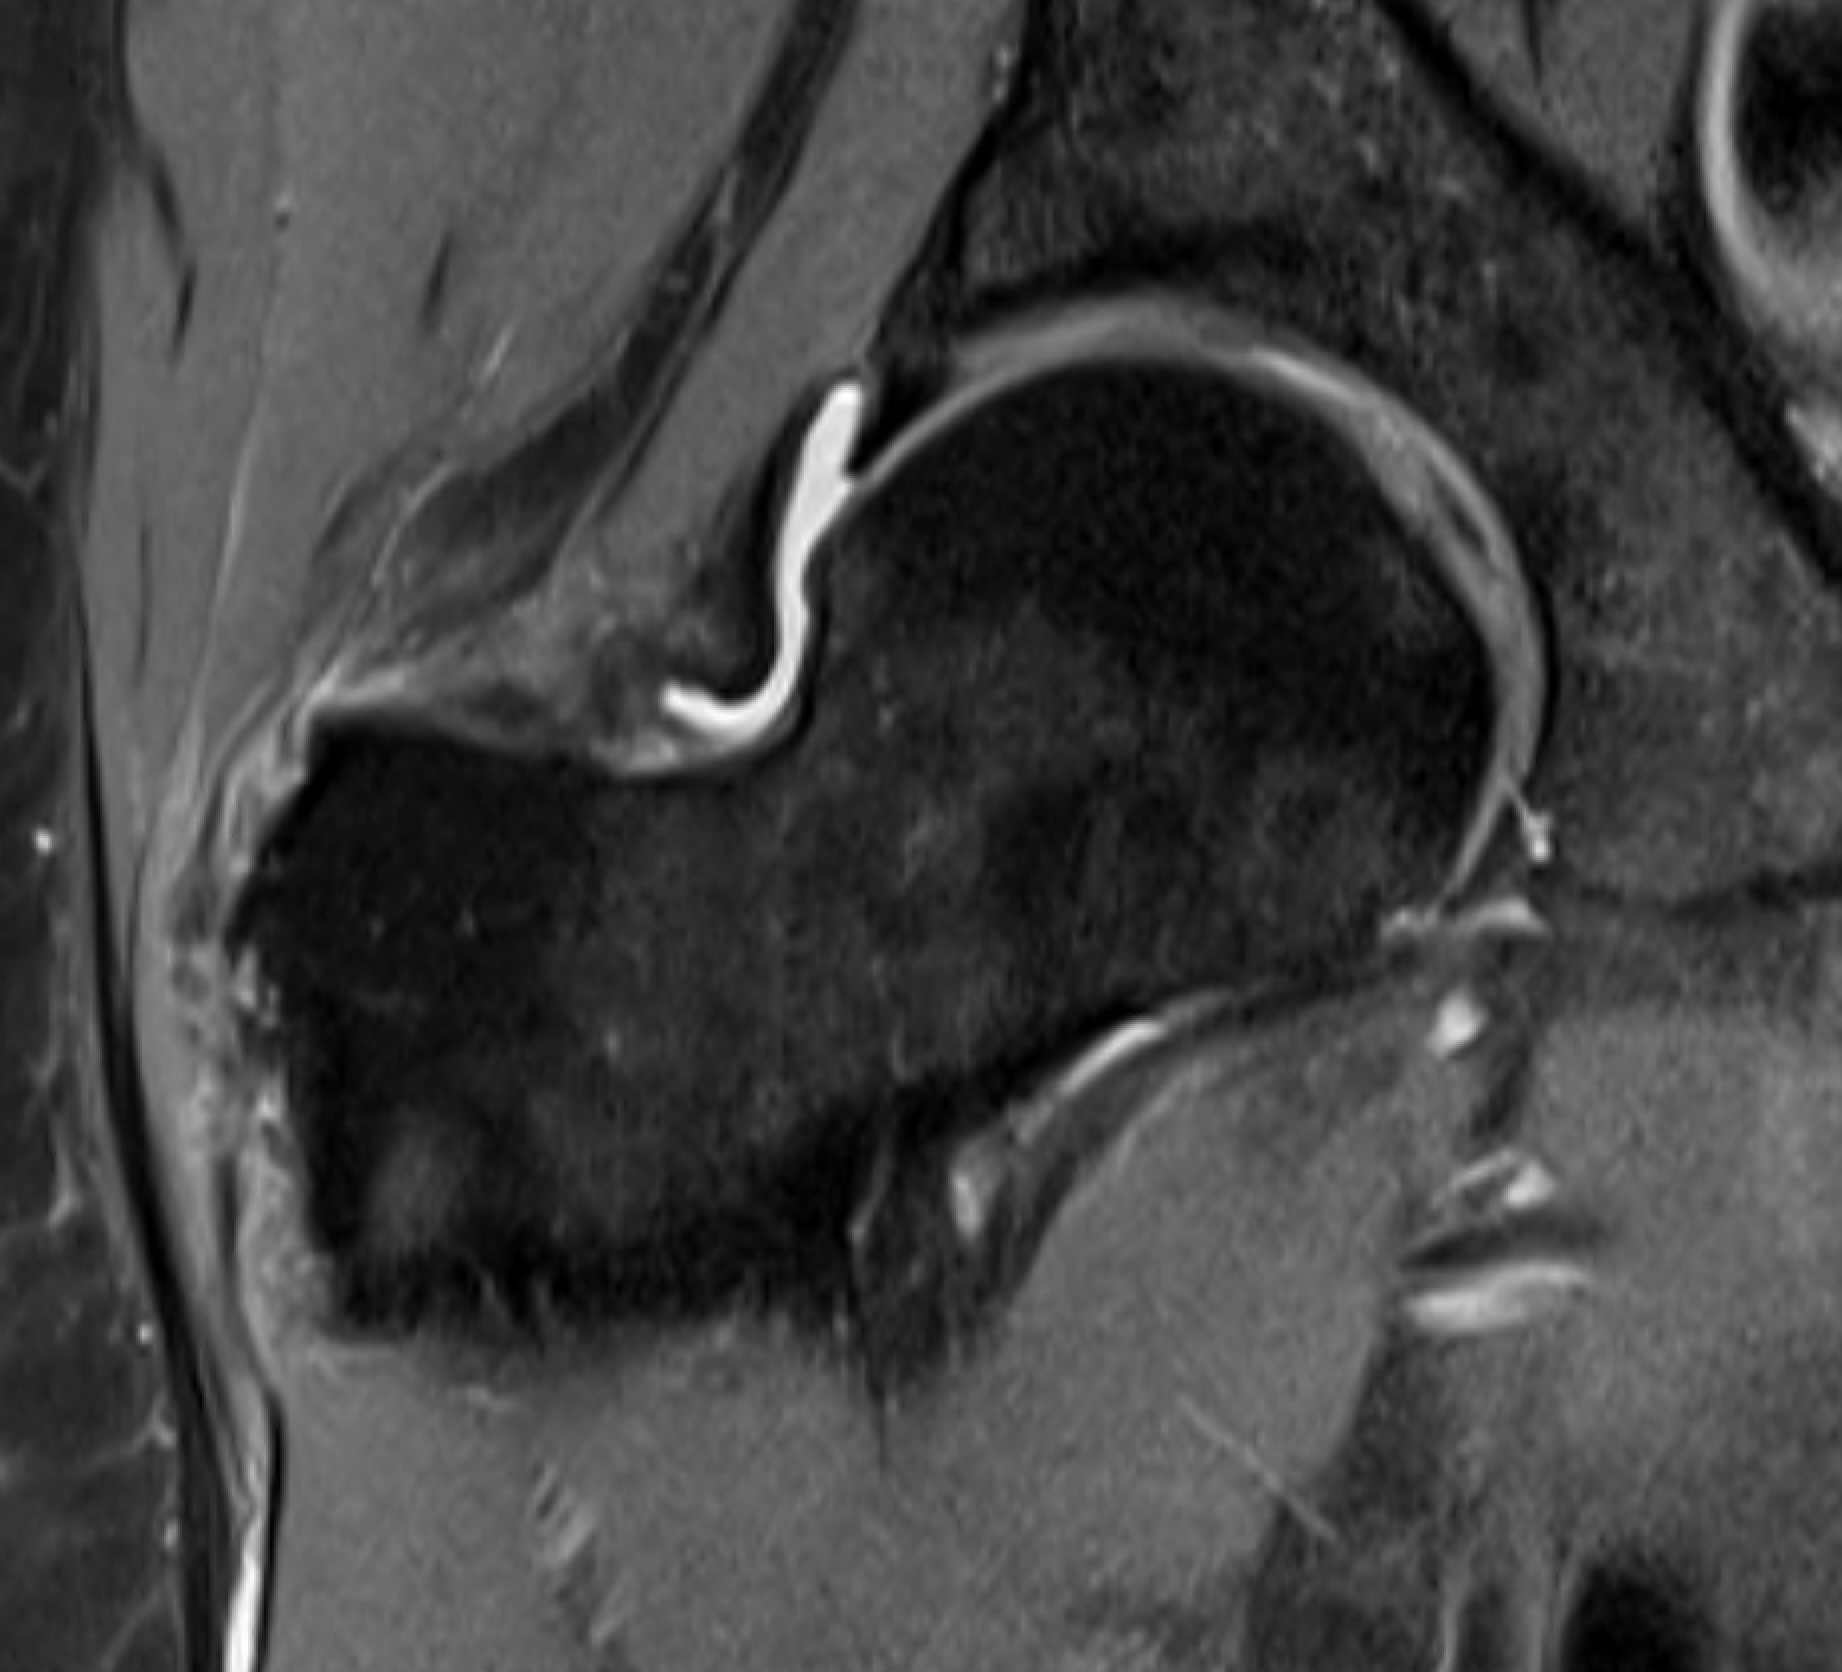

MRI

Acute tear gluteus medius